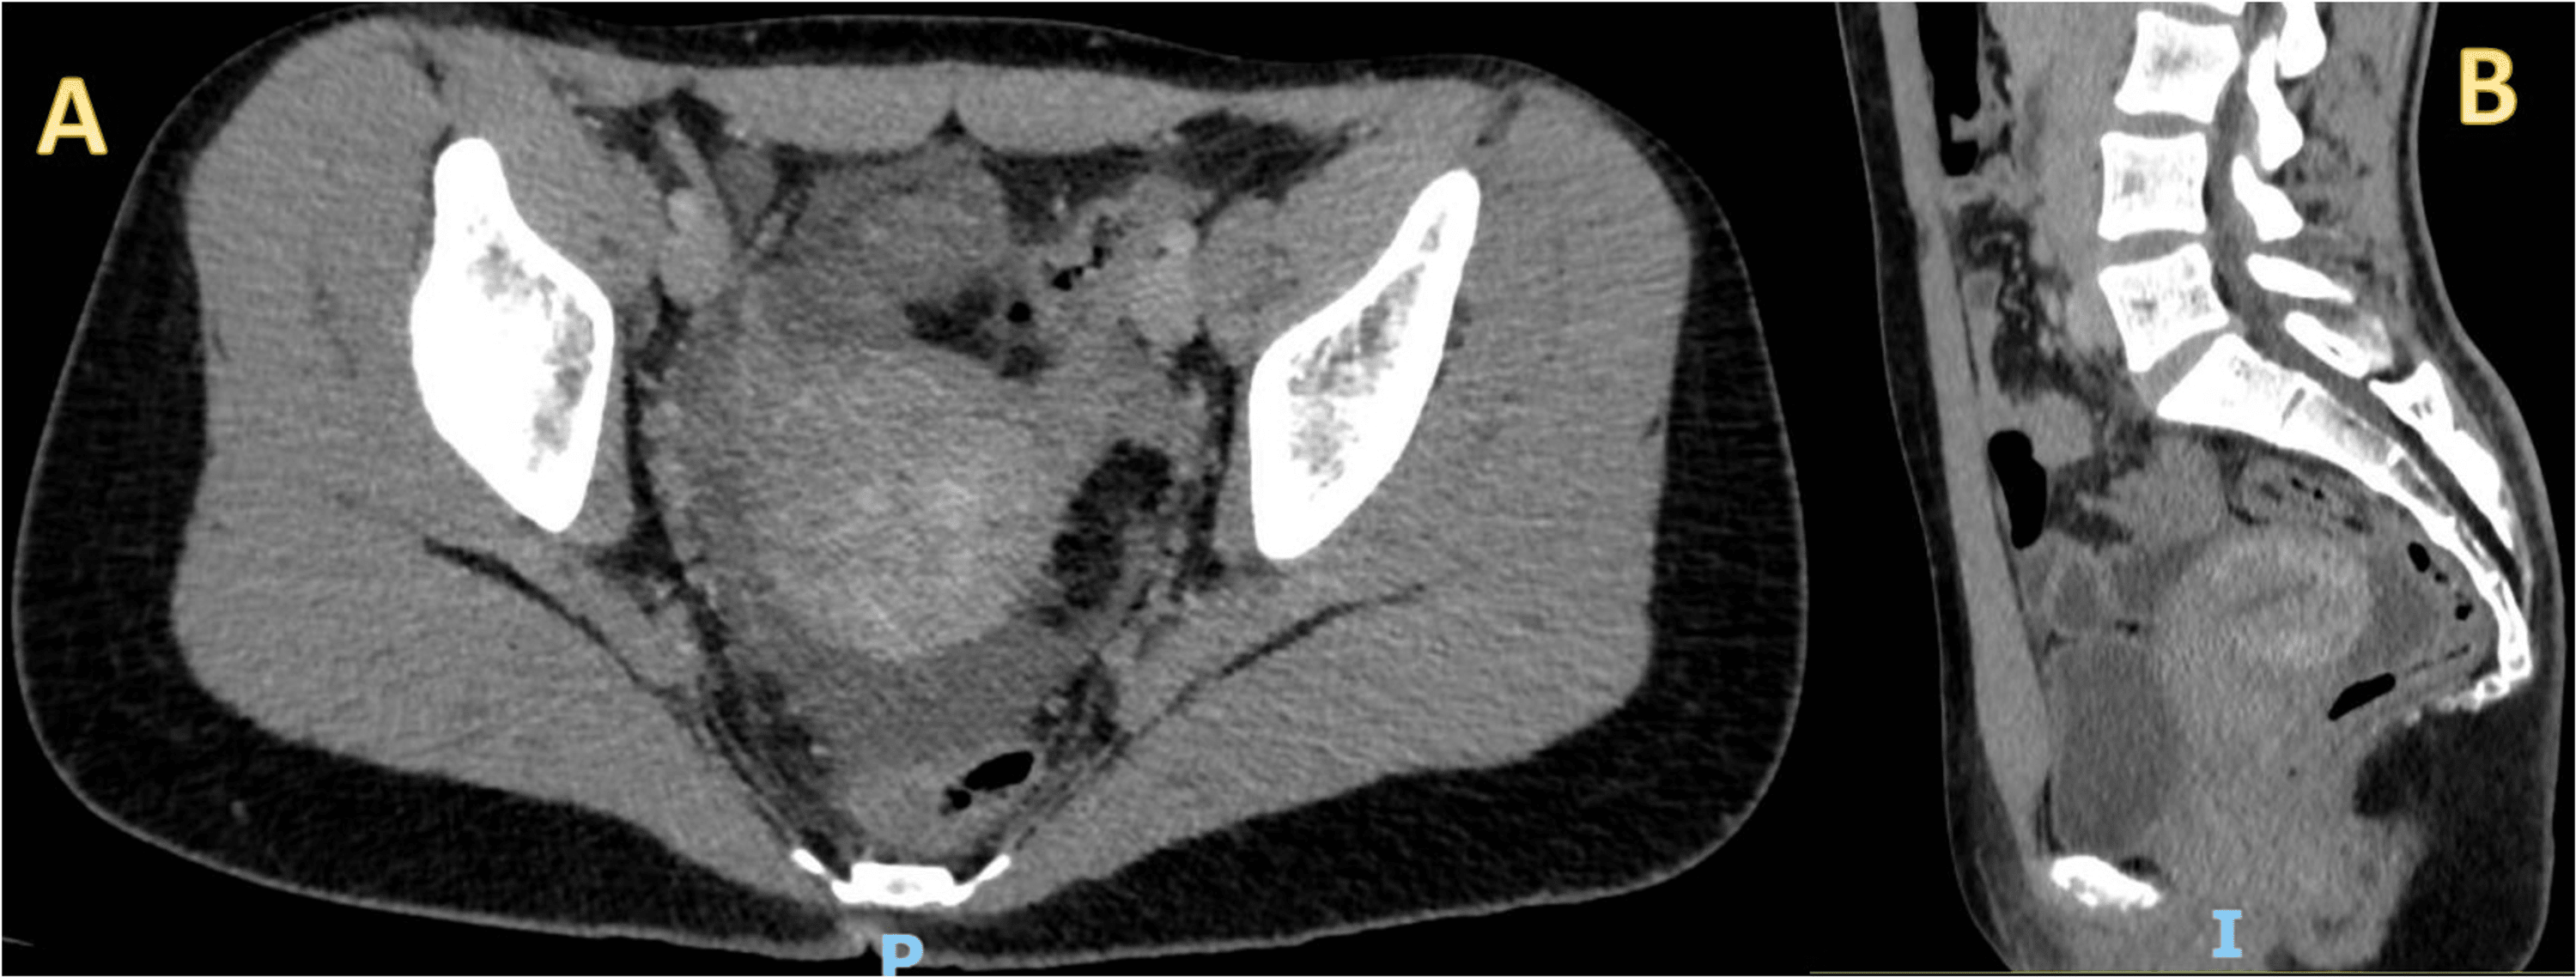

Trace abdominal free fluid Image Rectouterine Pouch Ultrasound pelvic ultrasound is usually the imaging modality of choice to evaluate pelvic masses as it is relatively inexpensive and. the rectouterine pouch (pouch of douglas) is the deep peritoneal space between the back of the uterus and the front of the proximal. the rectouterine pouch ( ta: free fluid in the cul de sac refers to. Rectouterine Pouch Ultrasound.